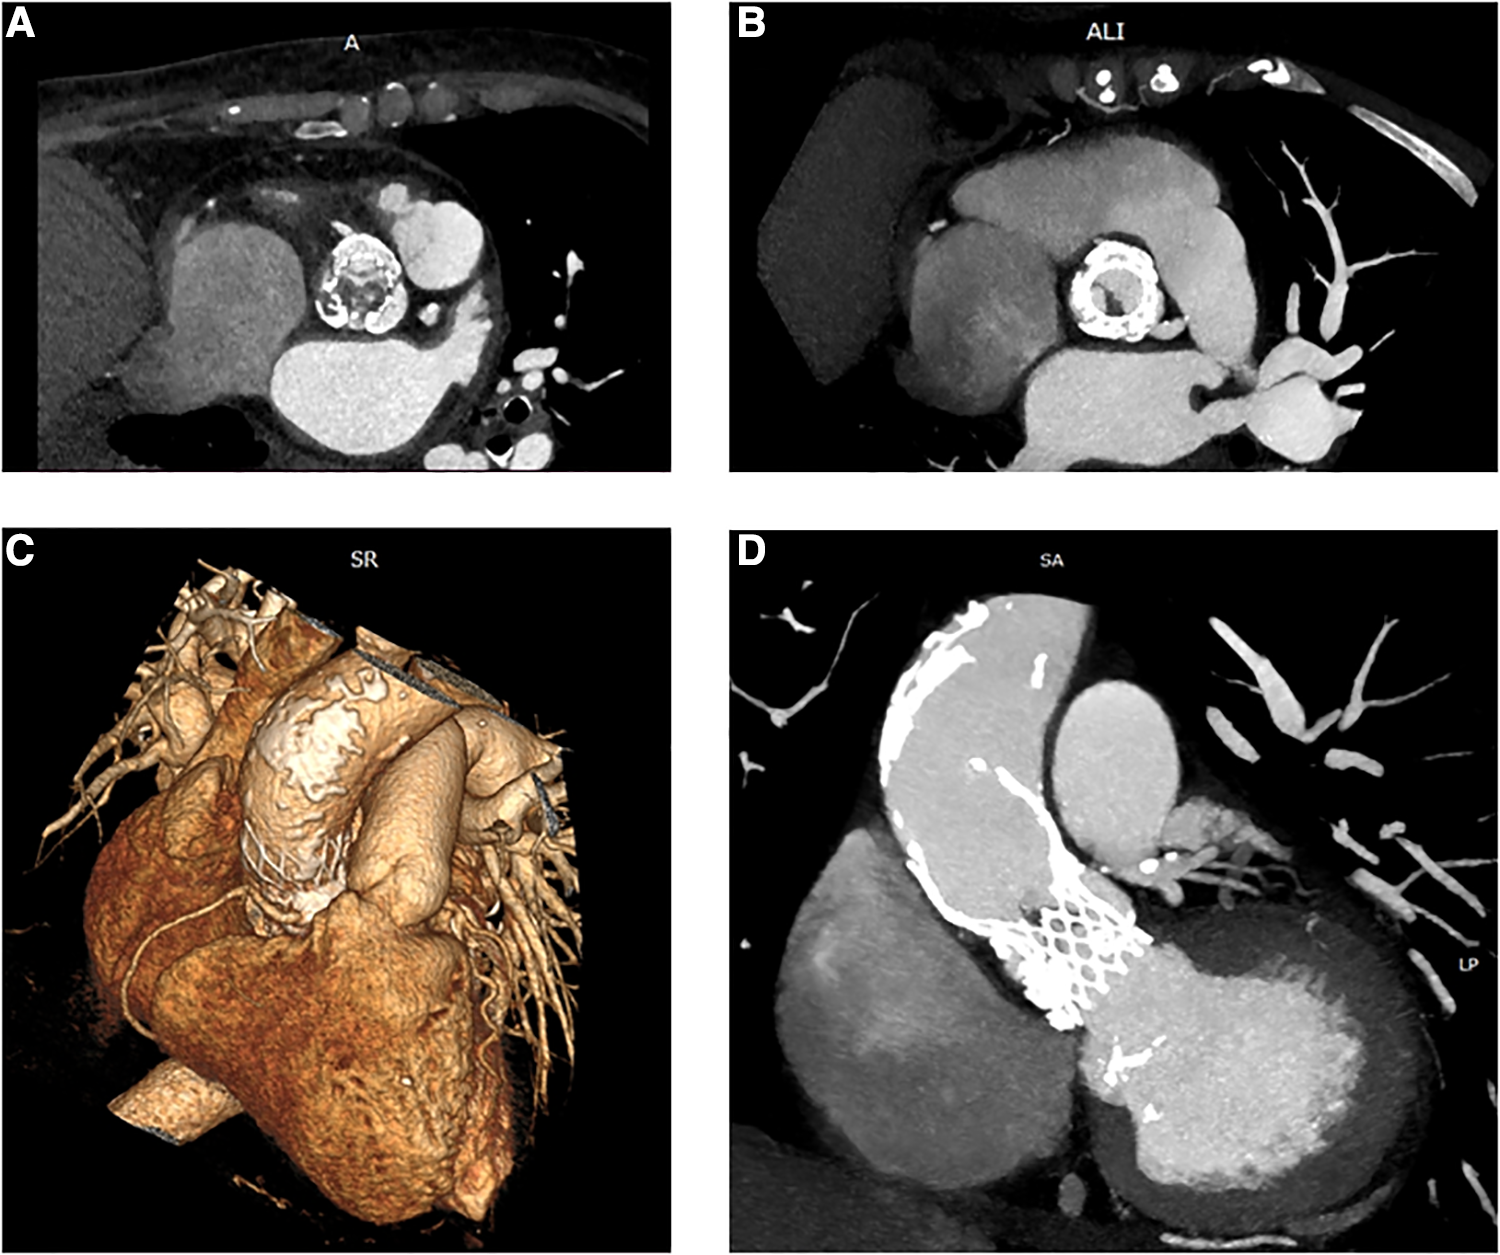

In November 2021, she was admitted to our emergency department due to fatigue, exertional dyspnea, and intermittent fever for 3 weeks, treated with empirical antibiotics. Electrocardiography demonstrated sinus rhythm, 70 beats/min, with features of left ventricle hypertrophy. The blood sample revealed moderate leukocytosis and 1.14 μg/L procalcitonin. Blood cultures were positive for Staphylococcus aureus. Both transthoracic echocardiogram (TTE) and transesophageal echocardiography (TEE) revealed large, mobile vegetation on the aortic prosthesis and non-structural valve dysfunction (NSVD) with a mean gradient of 54 mmHg. Angio-CT scanning showed thrombosis between the left coronary and non-coronary cusps of the prosthesis (Figure 1) and splenic embolization. Antibiotic therapy was started, guided by an antibiogram. Despite initial clinical improvement, 8 days after hospitalization, the patient developed a fever recurrence and initial hemodynamic deterioration requiring intensive care unit admission. Although the patient was previously discarded for surgery, TAVI-IE at this time was considered a surgical indication, despite the very high-risk score (STS PROM: 10.38%). After a full sternotomy, cardiopulmonary bypass (CPB) was set using the right axillary artery (by the interposition of a Dacron graft) and the right atrium. Aorta was clamped (in the upper zone 0), and Del Nido cardioplegia was administered. Through transverse aortotomy, the prosthesis was excised with the native aortic valve. The prosthesis was entirely covered by fibrotic tissue, and signs of endocarditis were also detected. Moreover, between the last part of the Valsalva sinus and the sinotubular junction, the aortic lumen was narrowed by a full-thickness circumferential calcified shelf, in this case described as an aortic sinotubular ridge. Due to this challenging anatomy, only the Perceval (Livanova, London, UK) S (small) sizer was suitable. In addition, considering the extremely calcified aorta and coronary ostia, the option to perform a Bentall-De Bono or an enlargement of the aortic root procedure was judged hazardous. Therefore, first, ascending aorta was replaced with a 24-mm Dacron tube to allow safe deployment of the sutureless valve, Perceval S, followed by ballooning. In addition, the aortic sinotubular ridge thickening did not allow placing the three standard guide stitches used for Perceval deployment. Therefore, only one guide stitch was used to parachute down the prosthesis (Figure 2). No extra stitches were used to anchor the valve to the Dacron graft. CPB was easily discontinued under TEE monitoring, demonstrating that the prosthesis was well-functioning. The explanted prosthesis was sent for microbiology analysis, and the result showed growth only for Gram-positive aerobic pathogens. The patient was extubated after 6 h and discharged to rehab on postoperative day 20. After 15 months of follow-up, no negative events were reported. Follow-up TTE showed preserved left ventricular ejection fraction (LVEF) and a well-functioning aortic prosthesis (mean gradient of 19 mmHg, no regurgitation).

Figure 1

Preoperative CT: axial view of the CoreValve prosthesis with vegetations in the left (A) and right (B) coronary cusps. 3D reconstruction of the ascending aorta with features of porcelain aorta (C). Multiplanar reconstruction (MPR) shows thrombosis and vegetation inside the CoreValve scaffold and prominent calcification of the aorta (D).